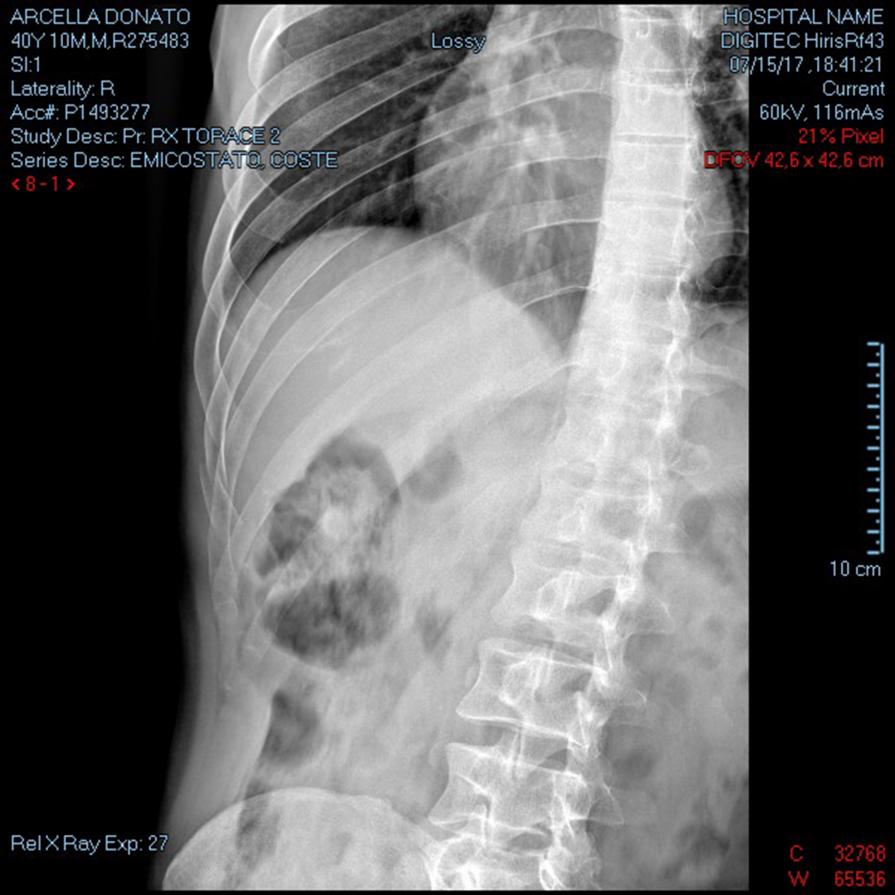

Emitorace DX  ( autoritratto  radiografia )

RX EMICOSTATO DX RX TORACE 2 PROIEZIONI RX TORACE ESPIRIUM Frattura lievemente scomposte all'arco posteriore della XI E XII costa e frattura scomposta all'arco anteriore dell'VIII costa dal lato destro, Frattura sostanzialmente composta all'arco medio-anteriore della X costa. Non evidenti falde pneumiche. Non apprezzabili versamenti pleurici né alterazioni parenchimali focali...